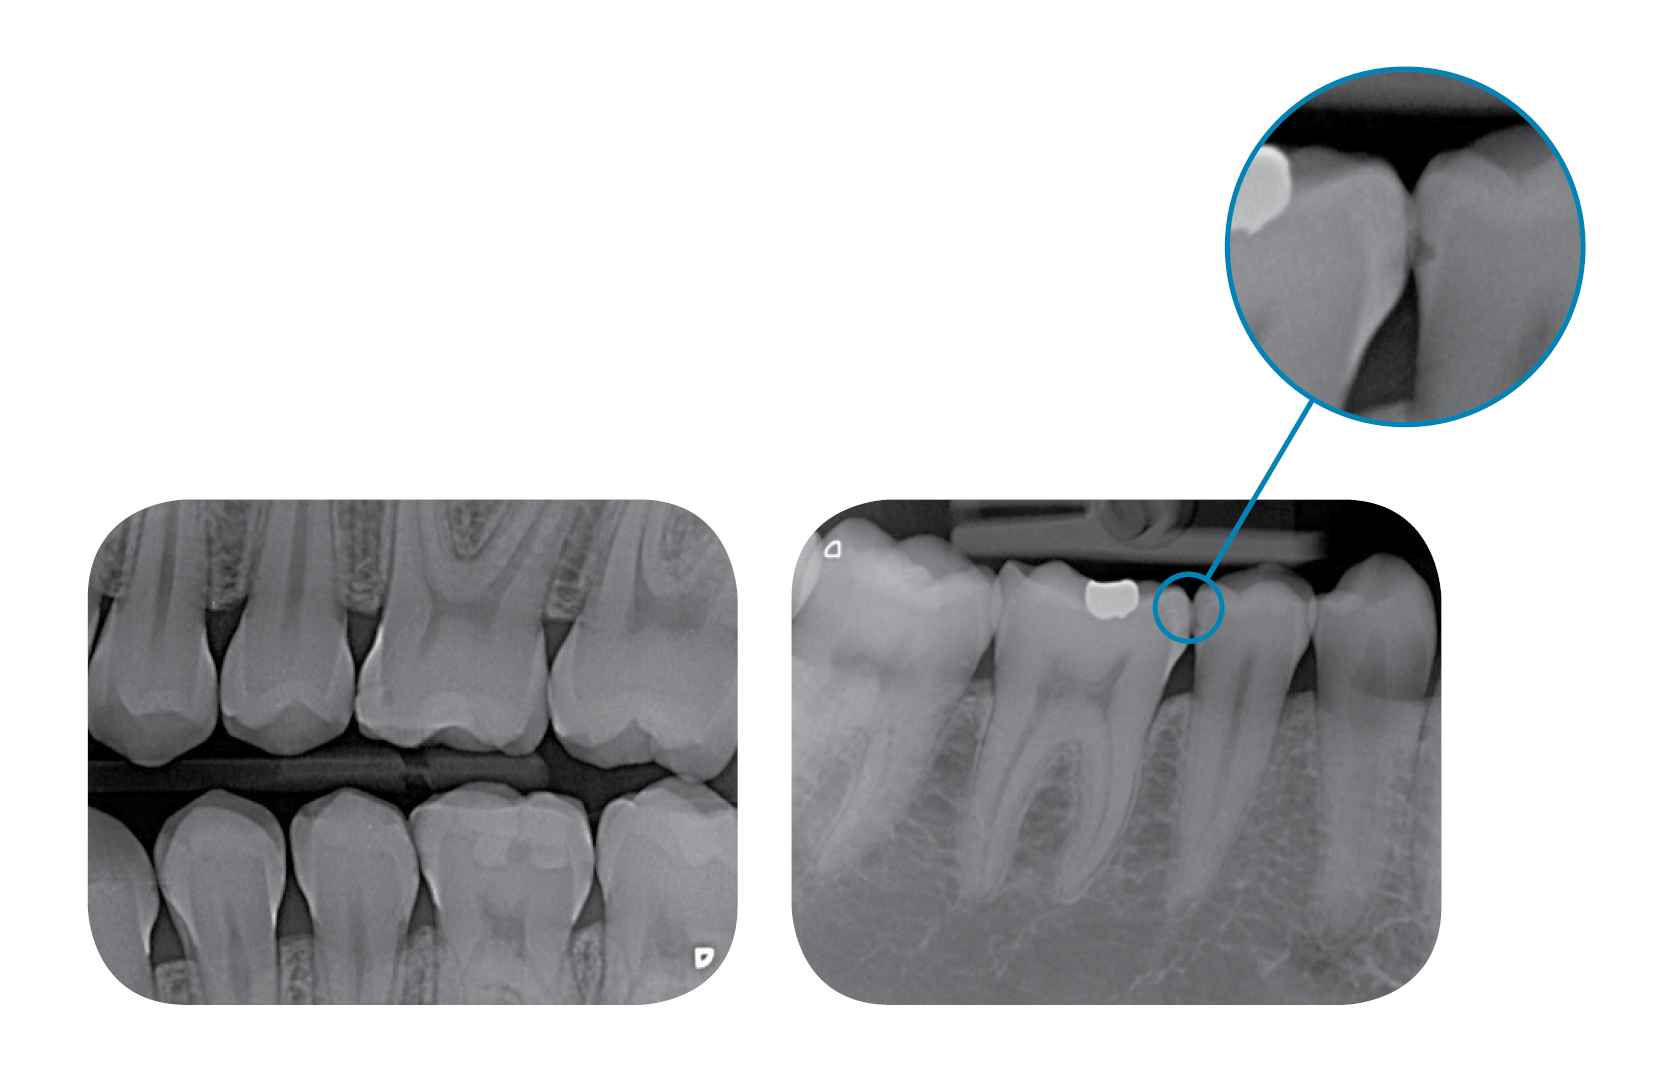

When changing to digital imaging plates you’ll notice that diagnostic reliability is increased thanks to the optimum detail recognition and sophisticated software support. With the VistaScan Mini range of PSP Scanners you’ll benefit from all the advantages of Durr image plate technology in its most compact form. The thin, flexible image plates are more pleasant for the patient and are particularly durable thanks to their special coating.

Since the introduction of conventional x-ray film in dentistry, Durr has been at the cutting edge of diagnostics in the dental surgery. Digital x-ray with Durr offers dentists images of the highest resolution to meet all diagnostic demands. This compact device is particularly easy to use and requires minimum space.

- Reliably resolve caries D1 lesions and endo instruments down to ISO 06